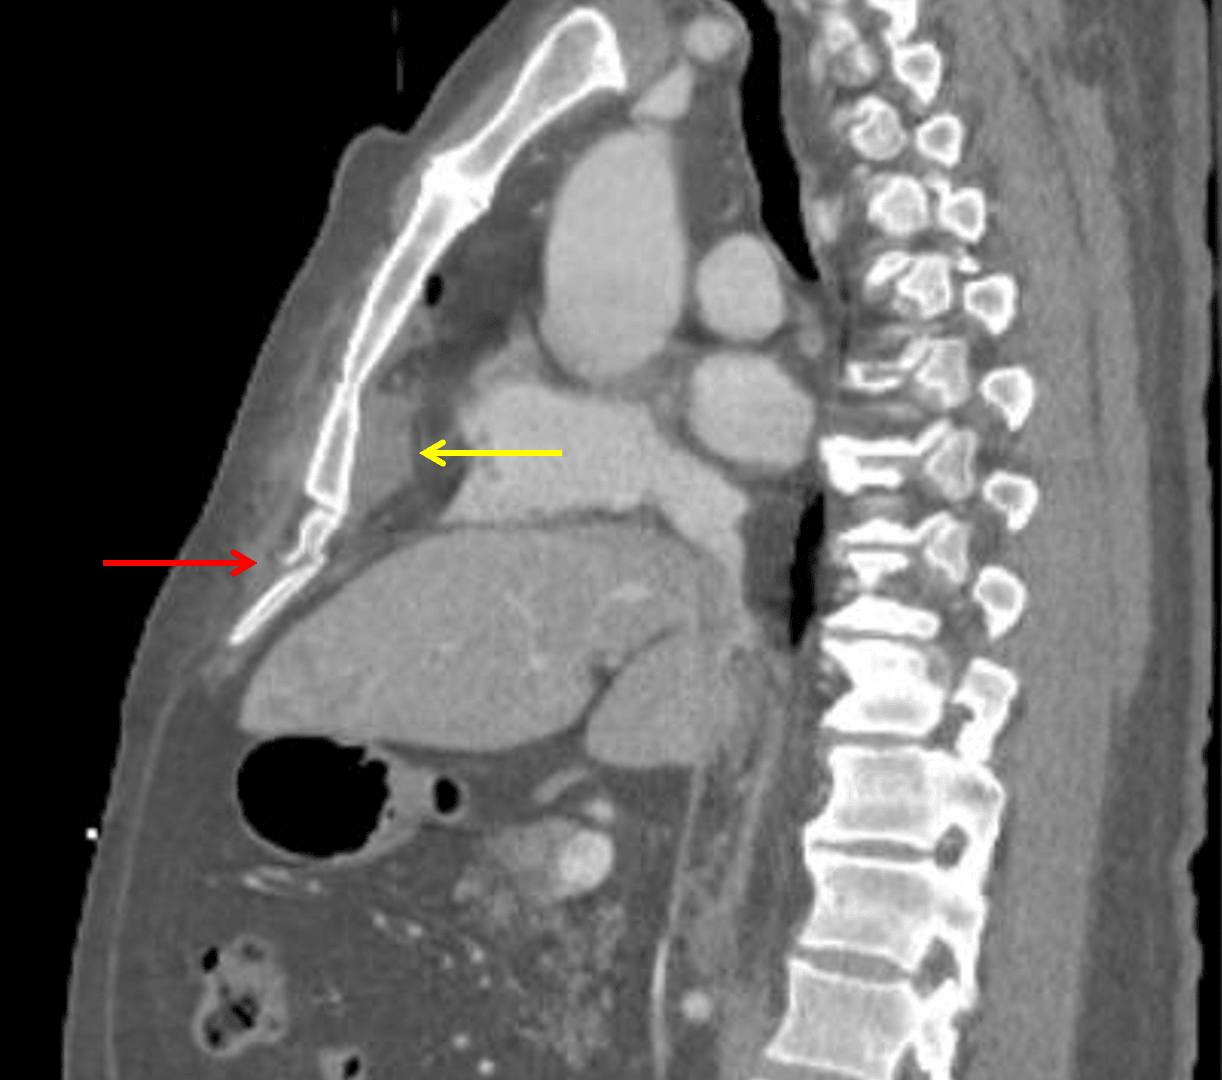

- Small lower anterior mediastinal hematoma without active extravasation

- Acute minimally displaced fracture of the xiphoid process

Acute fractures through the right costal cartilage and xiphoid process with a small lower mediastinal hematoma. No direct evidence of acute aortic injury.

Xiphoid process fracture (red arrow) and subjacent mediastinal hematoma (yellow arrow).